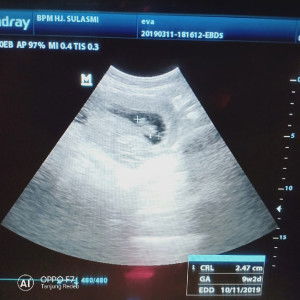

Assalamualaikum..bun mw tnya sya lg hamil usi kandungan 15 week...tp tiap berhubungan ama suami psti keluar darah,it normal ato knp ya bun?? Mhon info ny bun..ap ad yg prnah ngalami jga?